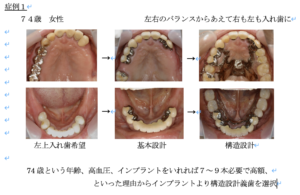

症例1